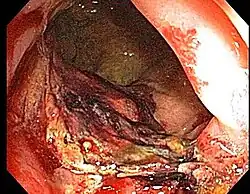

- Etiology: obliterative endarteritis and chronic mucosal ischemia, leading to progressive epithelial atrophy and fibrosis. Ultimately, development of a chronically ischemic intestine prone to fibrosis and bleeding

- Symptoms: diarrhea, obstructed defecation (if strictures), bleeding, rectal pain, rectal urgency, and fecal incontinence. Rarely fistulas, SBO

- Diagnosis: colonoscopy, barium studies if suspecting strictures and fistulas

- Endoscopy (Argon plasma coagulation) - benefit for bleeding